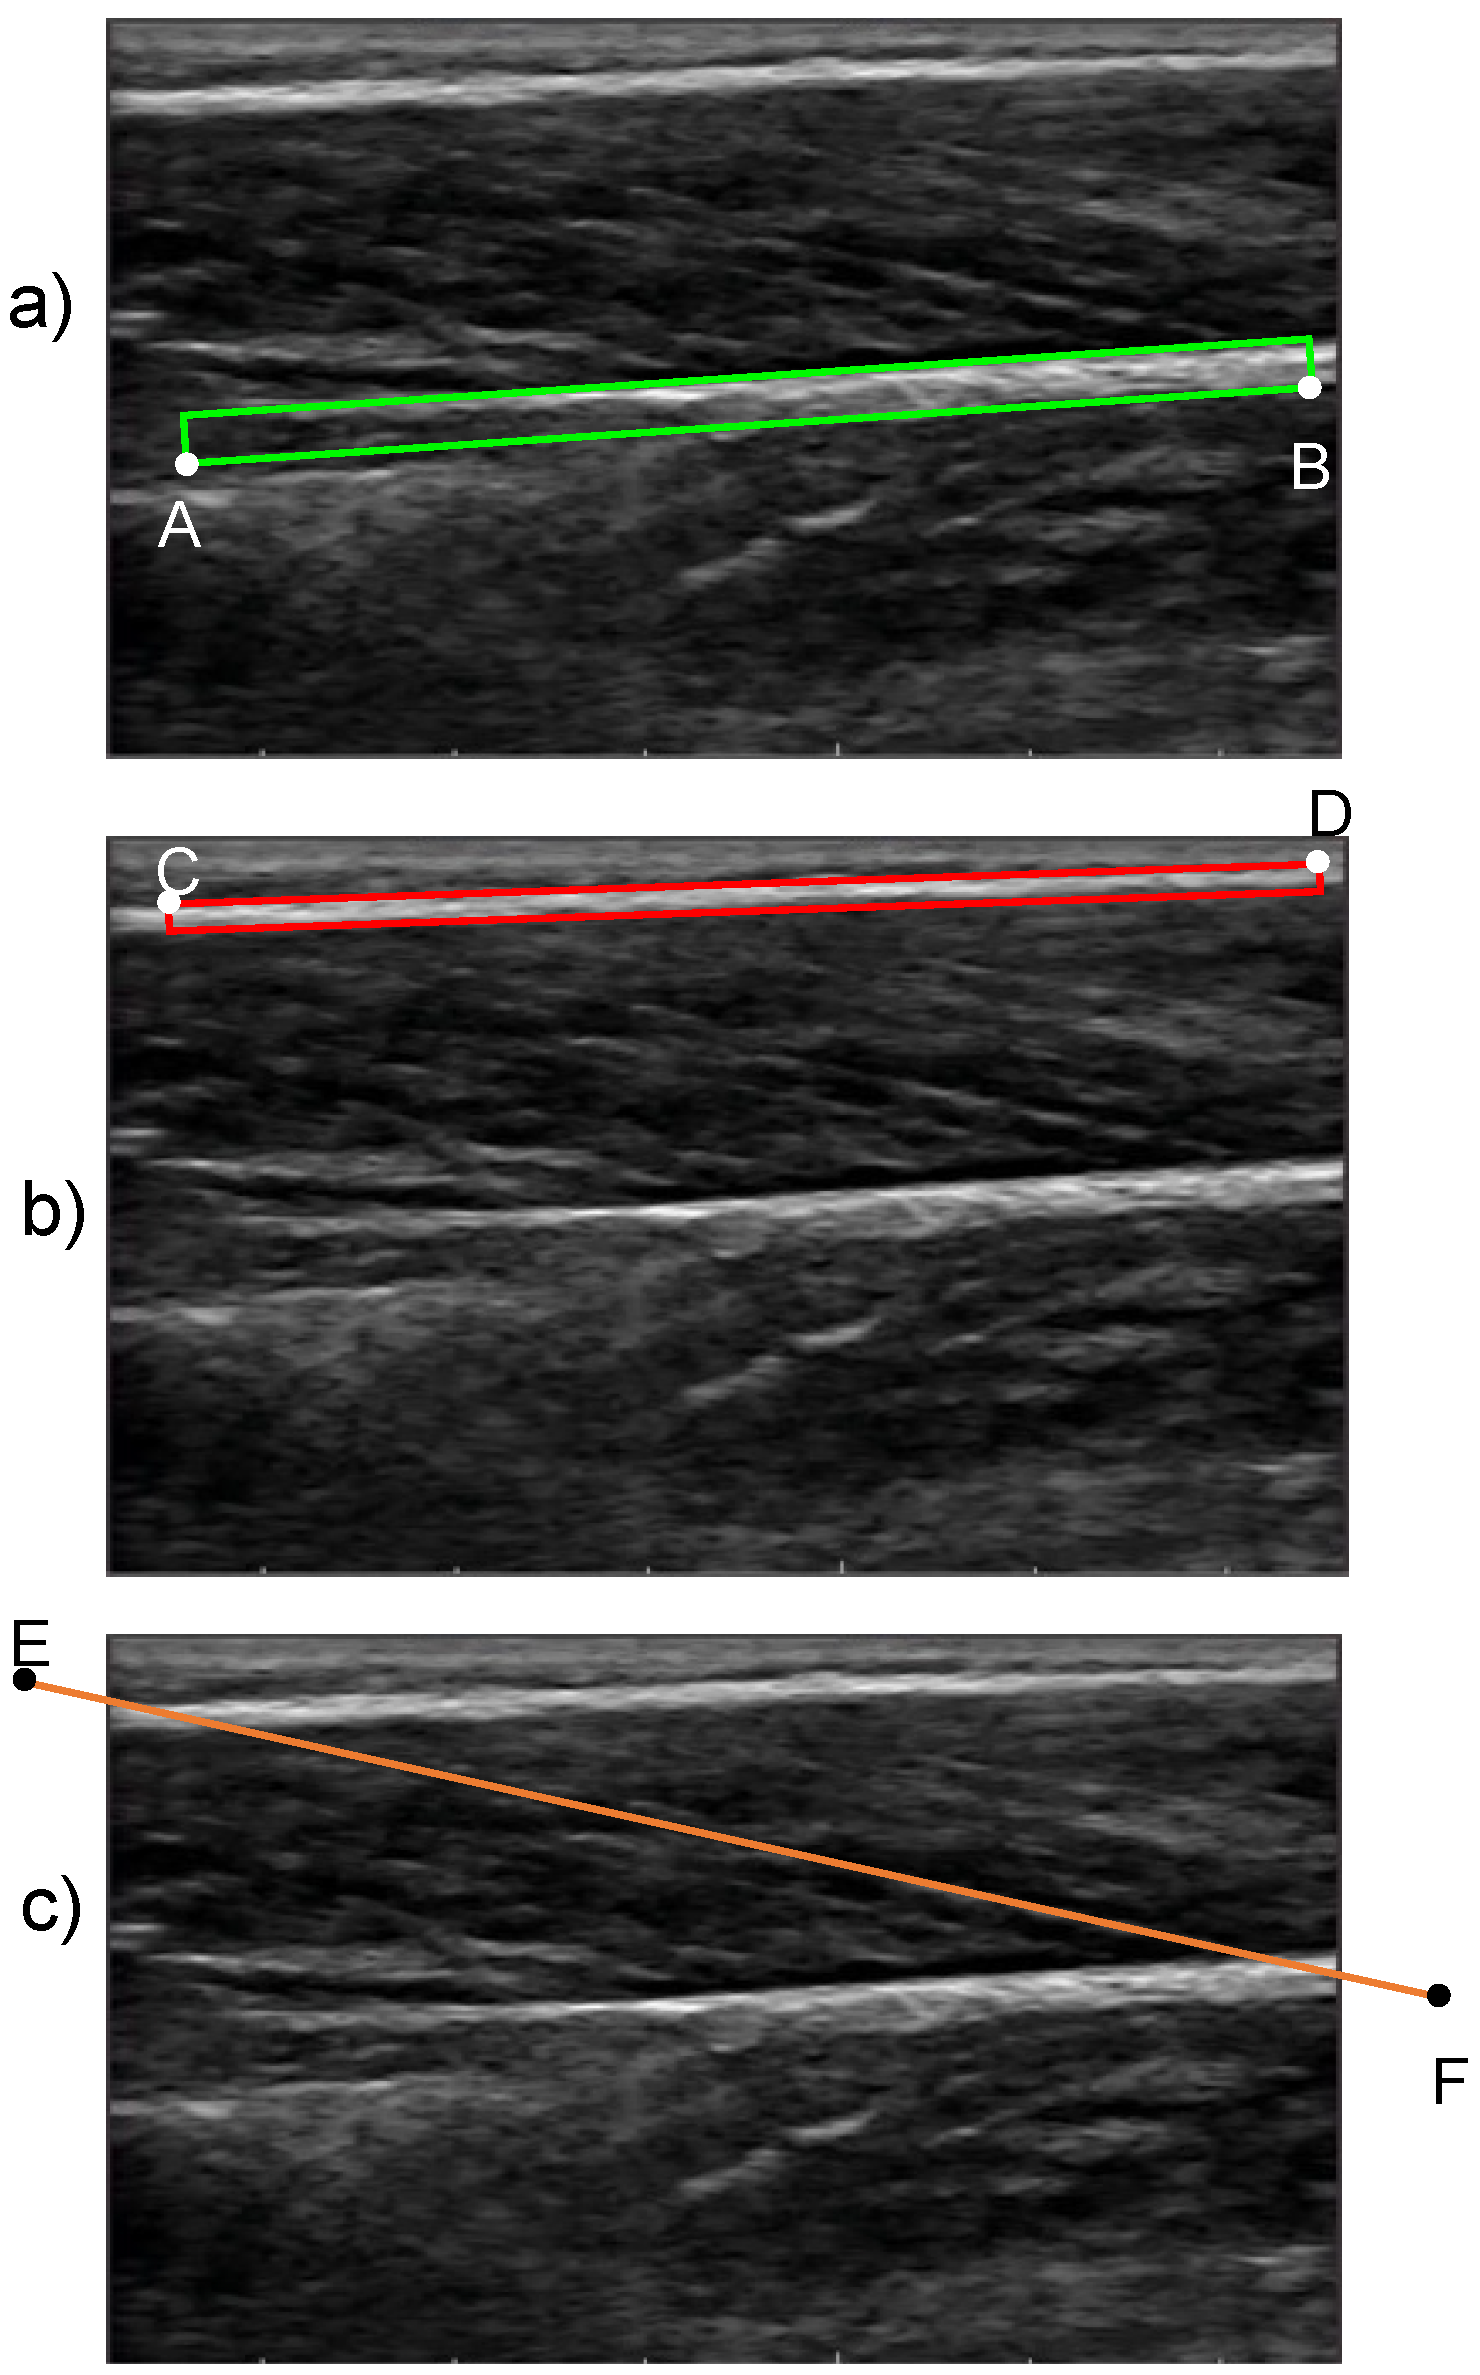

The proposed method for the quantification of FL and PA begins with an initialization procedure where the user defines two boxes: one that encloses the superficial and the other that encloses the deep aponeuroses in the reference frame (frame 1). For the deep aponeurosis, starting from the left end, the user defines a line on the bottom boundary of the fascicle band (line AB in Figure 3a) and enters the thickness of the box. Similarly, for the superficial aponeurosis, starting from the left end, the user defines a line on the top boundary of the fascicle band (line CD in Figure 3b) and enters the thickness of the box. The thickness of the boxes was chosen on a trial-and-error basis such that at least ≈90% of the aponeurosis area was enclosed by the initialized boxes. A preliminary sensitivity analysis confirmed that the outcome of the algorithm was not sensitive to the thickness of the initialized boxes (Appendix A). To complete the initialization, the user draws a straight line that is parallel to the direction of fascicles in the fascicle band (line EF in Figure 3c). This line does not need to closely match a specific fascicle. The boxes that enclose the deep and superficial aponeuroses is the input to stage 2, while the fascicle direction line is used as one of the inputs to stage 3.

Figure 3.

Initialization boxes that enclose (a) the deep aponeurosis and (b) the superficial aponeurosis. The respective lines that are drawn by the user are denoted as AB and CD for the deep and superficial aponeurosis, respectively. (c) The line that is drawn by the user (EF) to initialize the fascicle direction.